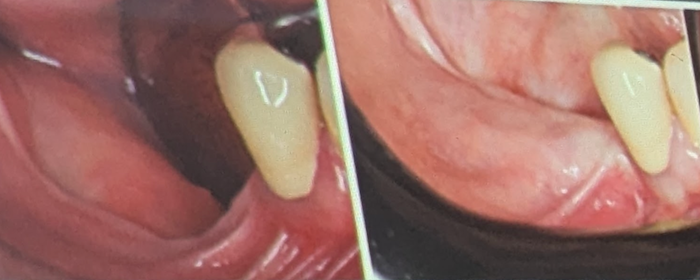

Place implants and thicken tissue

Improve tissue and place final teeth

Case performed by Dr. Robert Silva – Instagram